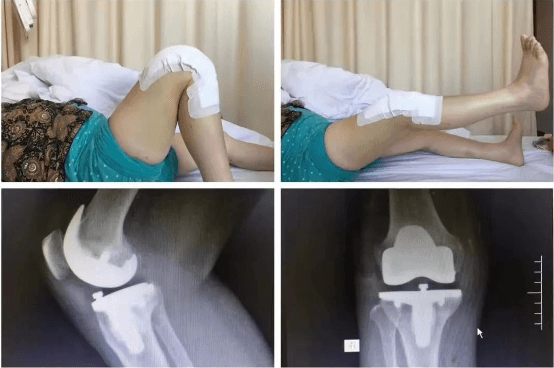

清晨剛上班的骨科門診,來(lái)了幾位復(fù)診患者,分別是肩袖損傷術(shù)后、髕骨脫位術(shù)后、膝關(guān)節(jié)前交叉韌帶斷裂重建術(shù)后,膝關(guān)節(jié)半月板撕裂修復(fù)縫合術(shù)后的患者?;颊咭?jiàn)到李鵬主任立即都非常熱情的迎了上來(lái),李主任也耐心的進(jìn)行了接診,并一一為患者詳細(xì)、專業(yè)的進(jìn)行術(shù)后康復(fù)指導(dǎo)?;颊咚邮苁中g(shù)的肩、膝關(guān)節(jié),活動(dòng)范圍明顯改善,他還為患者擬定下一階段的康復(fù)動(dòng)作計(jì)劃,繼續(xù)進(jìn)行主被動(dòng)鍛煉,肌力訓(xùn)練,日常生活行為能力訓(xùn)練等動(dòng)作。診療完成后李主任讓患者添加微信,每周拍自己的康復(fù)鍛煉視頻發(fā)給自己,以便對(duì)患者的動(dòng)作及時(shí)進(jìn)行指導(dǎo)。這一舉動(dòng)立即讓患者及家屬感受到了作為醫(yī)生的良苦用心,他說(shuō):“要讓患者挺直腰桿走回家”。這幾位復(fù)診患者都有一個(gè)共同特點(diǎn),就是他們受傷后都接受了運(yùn)動(dòng)醫(yī)學(xué)亞??频年P(guān)節(jié)鏡微創(chuàng)手術(shù),手術(shù)后3-5天即可出院,創(chuàng)傷小、恢復(fù)快,他們對(duì)手術(shù)效果非常滿意。

通過(guò)不斷的學(xué)習(xí)國(guó)際國(guó)內(nèi)前沿的理論知識(shí),李鵬帶領(lǐng)亞專業(yè)團(tuán)隊(duì)醫(yī)護(hù)人員,在我院較早提出術(shù)前康復(fù)及無(wú)痛病房的理念,將EARS理念融入于患者術(shù)前、術(shù)中、術(shù)后治療過(guò)程中,通過(guò)與麻醉科合作,圍手術(shù)期的管理及手術(shù)技術(shù)的不斷提高,實(shí)現(xiàn)術(shù)后幾乎無(wú)痛。在臨床醫(yī)學(xué)中,骨科手術(shù)和康復(fù)是相輔相成的,他帶領(lǐng)團(tuán)隊(duì)術(shù)前即開(kāi)始正規(guī)的運(yùn)動(dòng)康復(fù),保證患者手術(shù)成功,促使患者術(shù)后有效、快速地恢復(fù),早日回歸生活、重返運(yùn)動(dòng)。

髕骨脫位手術(shù)

擅長(zhǎng)治療各種骨關(guān)節(jié)外傷、骨關(guān)節(jié)疾病。手術(shù)方面擅長(zhǎng)髖、膝關(guān)節(jié)置換術(shù)、膝關(guān)節(jié)單髁置換術(shù)、脛骨高位截骨術(shù)、股骨頸骨折及轉(zhuǎn)子間骨折等手術(shù)。富血小板血漿(PRP)治療骨關(guān)節(jié)炎。擅長(zhǎng)關(guān)節(jié)鏡下膝關(guān)節(jié)交叉韌帶重建、半月板損傷縫合、髕骨脫位、肩袖修補(bǔ),肩峰撞擊征、鈣化性肌腱炎,肱二頭肌長(zhǎng)頭腱炎,髖關(guān)節(jié)盂唇損傷、髖關(guān)節(jié)撞擊征、踝關(guān)節(jié)不穩(wěn)、踝關(guān)節(jié)韌帶損傷、肩關(guān)節(jié)不穩(wěn)、肩周炎、各類關(guān)節(jié)內(nèi)骨折、關(guān)節(jié)脫位的手術(shù)治療。